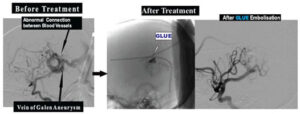

Embolisation of Vein Of Galen Aneurysmal malformation (VOGAM) :

These are abnormal Connections between Arteries and Veins in Brain causing increase in pressure in Brain Veins causing Heart Failure, Stunted Growth or Fits/ Epilepsy.

With Interventional Neuroradiological ,Without opening the Skull ; these Connections between Arteries Abnormal and Veins in Brain can be treated by technique of Glue Embolisation .

Example: 4 month old baby boy presented with Stunted Growth and large head due to Vein Of Galen Aneurysmal malformation (VOGAM). After GLUE Embolisation of Vein Of Galen Aneurysmal malformation (VOGAM), now he is growing at normal stages.